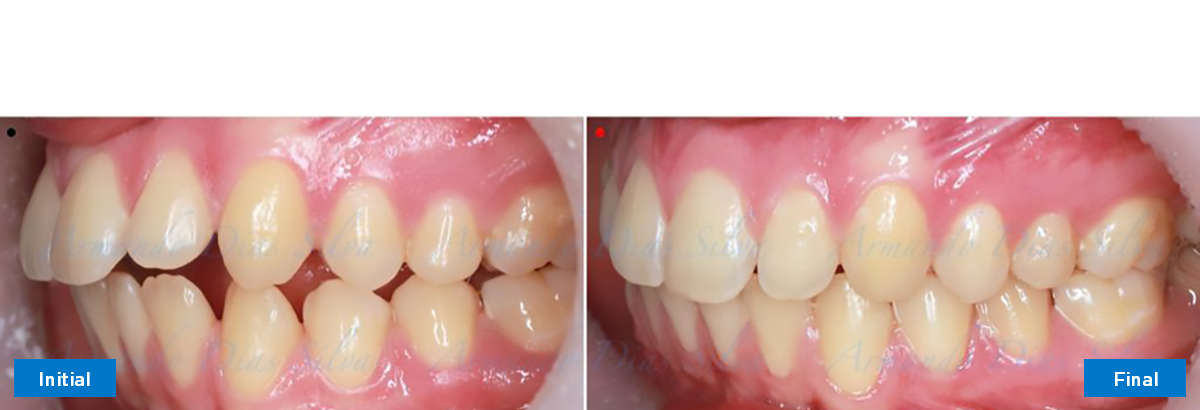

Clase II, Div. 1: Protrusión del incisivo central y espacios anteriores (SureSmile® Aligners)

Principal queja del paciente: Protrusión del incisivo central y mordida abierta. El paciente rechaza la expansión del arco palatino (MARPE) y las extracciones.

Este paciente adolescente presenta molares de Clase II y no le gusta su mordida abierta ni lo protrusivos que son sus dientes frontales. Por sus fotografías faciales, parece que su mandíbula es retrognática o le falta volumen en la barbilla. El historial del paciente también indica que existe un problema funcional al no haber guía de los incisivos.

Diagnóstico

• Molares de clase II

• Diastema

• Espaciamiento leve de las arcadas superior e inferior (deficiencia transversal de 3,45 mm)

• El primer molar superior derecho está en una posición más mesial que el primer molar superior izquierdo

• Deficiencia transversal maxilar leve (3,45 mm)

• Incisivos superiores e inferiores proclinados

• Orientación canina desfavorable

Se logran todos los objetivos principales:

• Molares de clase I logrados con distalización y sin elásticos

• Sin cambios en la posición del cóndilo

• Sin expansión maxilar, respetando la envoltura periodontal

• Incisivos inferiores retroinclinados, que mejoran la estabilidad a largo plazo